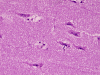

The overall tissue preservation is less than optimal because of postmortem autolysis. Panel A and B are taken from the cerebellum. The molecular layer, Purkinje cell layer, and internal granular layer are included (Panel A). Solitary eosinophilic intracytoplasmic inclusions of variable size are present in the Purkinje cells. No inflammatory cell infiltration is present in the cerebellum. The vacuolar spaces (Panel B) is partly due to autolysis and partly due to hypoxic/ischemic changes. Pyramidal cells in the hippocampus (Panel C), cortical neurons in parietal lobe (Panel D) and other neocortical areas adopted an elongated and contracted contour with loss of nuclear details. These are histologic features consistent with hypoxic/ischemic changes. Similar to the cerebellum, solitary eosinophilic cytoplasmic inclusion bodies are present and there is no inflammatory cell infiltration. Multiple eosinophilic cytoplasmic inclusion bodies within a single neuron are occasionally found. Some of these neurons containing multiple inclusions from the substantia nigra are illustrated in Panel E. Although inflammatory cell infiltration is scant in the cerebrum and cerebellum, perivascular chronic inflammatory cell infiltrations are common in the medulla (Panel F and G), in the paravertebral sympathetic ganglion (Panel H and I) and in the spinal cord (not shown). Intracytoplasmic inclusions, however, are not found in the medulla, spinal cord, and paravertebral sympathetic ganglion. Under the electron microscope, rod-shape or bullet-shaped viral particles are found (Panel J).

The brain and spinal cord may appear swollen but are usually free of focal lesions. Histopathologically, rabies is a widespread polioencephalomyelitis. Leptomeningeal and parenchymal perivascular lymphocytic infiltrations are usually present but often not intense. Neuronophagia can also be seen. The amount of inflammation of the case under discussion is, in fact, on the intense side of the scale. The pathognomonic Negri bodies 10, 11, 12 are sharply delineated, round to oval, eosinophilic, neuronal cytoplasmic inclusions; first described by Negri in 1903 10. These inclusions are often solitary but may also be multiple in a single neuron. Lyssa bodies refer to less well delineated and more pleomorphic neuronal cytoplasmic viral inclusions. Babes’ nodules refer to clusters of microglia that remain after destruction of neurons. When immunohistochemistry is employed, the distributions of viral antigen are far more extensive than that estimated by conventional light microscopy 13. Negri body and rabies viral antigen as demonstrated by immunohistochemistry are most commonly seen in large neurons of the hippocampus (Pyramidal cells), cerebellum (Purkinje cells), thalamus, basal ganglia, cerebral cortex and in the brain stem, especially gray matter of the pons and medulla. They are also found in spinal cord motor neurons and dorsal root ganglion, especially in the paralytic form.  Immunohistochemistry also demonstrated rabies viral antigen in astrocytes and oligodendrocytes 13. Characteristically, a striking discrepancy between the degree of inflammation and amount of inclusion bodies is observed, as in our case, in many cases.